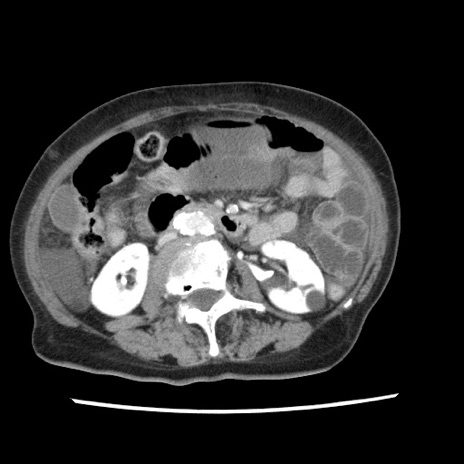

冠状断像

【症例】80歳代女性

【主訴】腹痛

【現病歴】8時間前から腹痛あり来院。

【既往歴】糖尿病、脂質異常症、子宮体癌にて子宮全摘術

【身体所見】意識清明・会話良好だが腹痛で苦悶様、全腹部にわたって反跳痛と圧痛あり

【データ】WBC 13600、CRP 0.14、LDH 224、CK 90